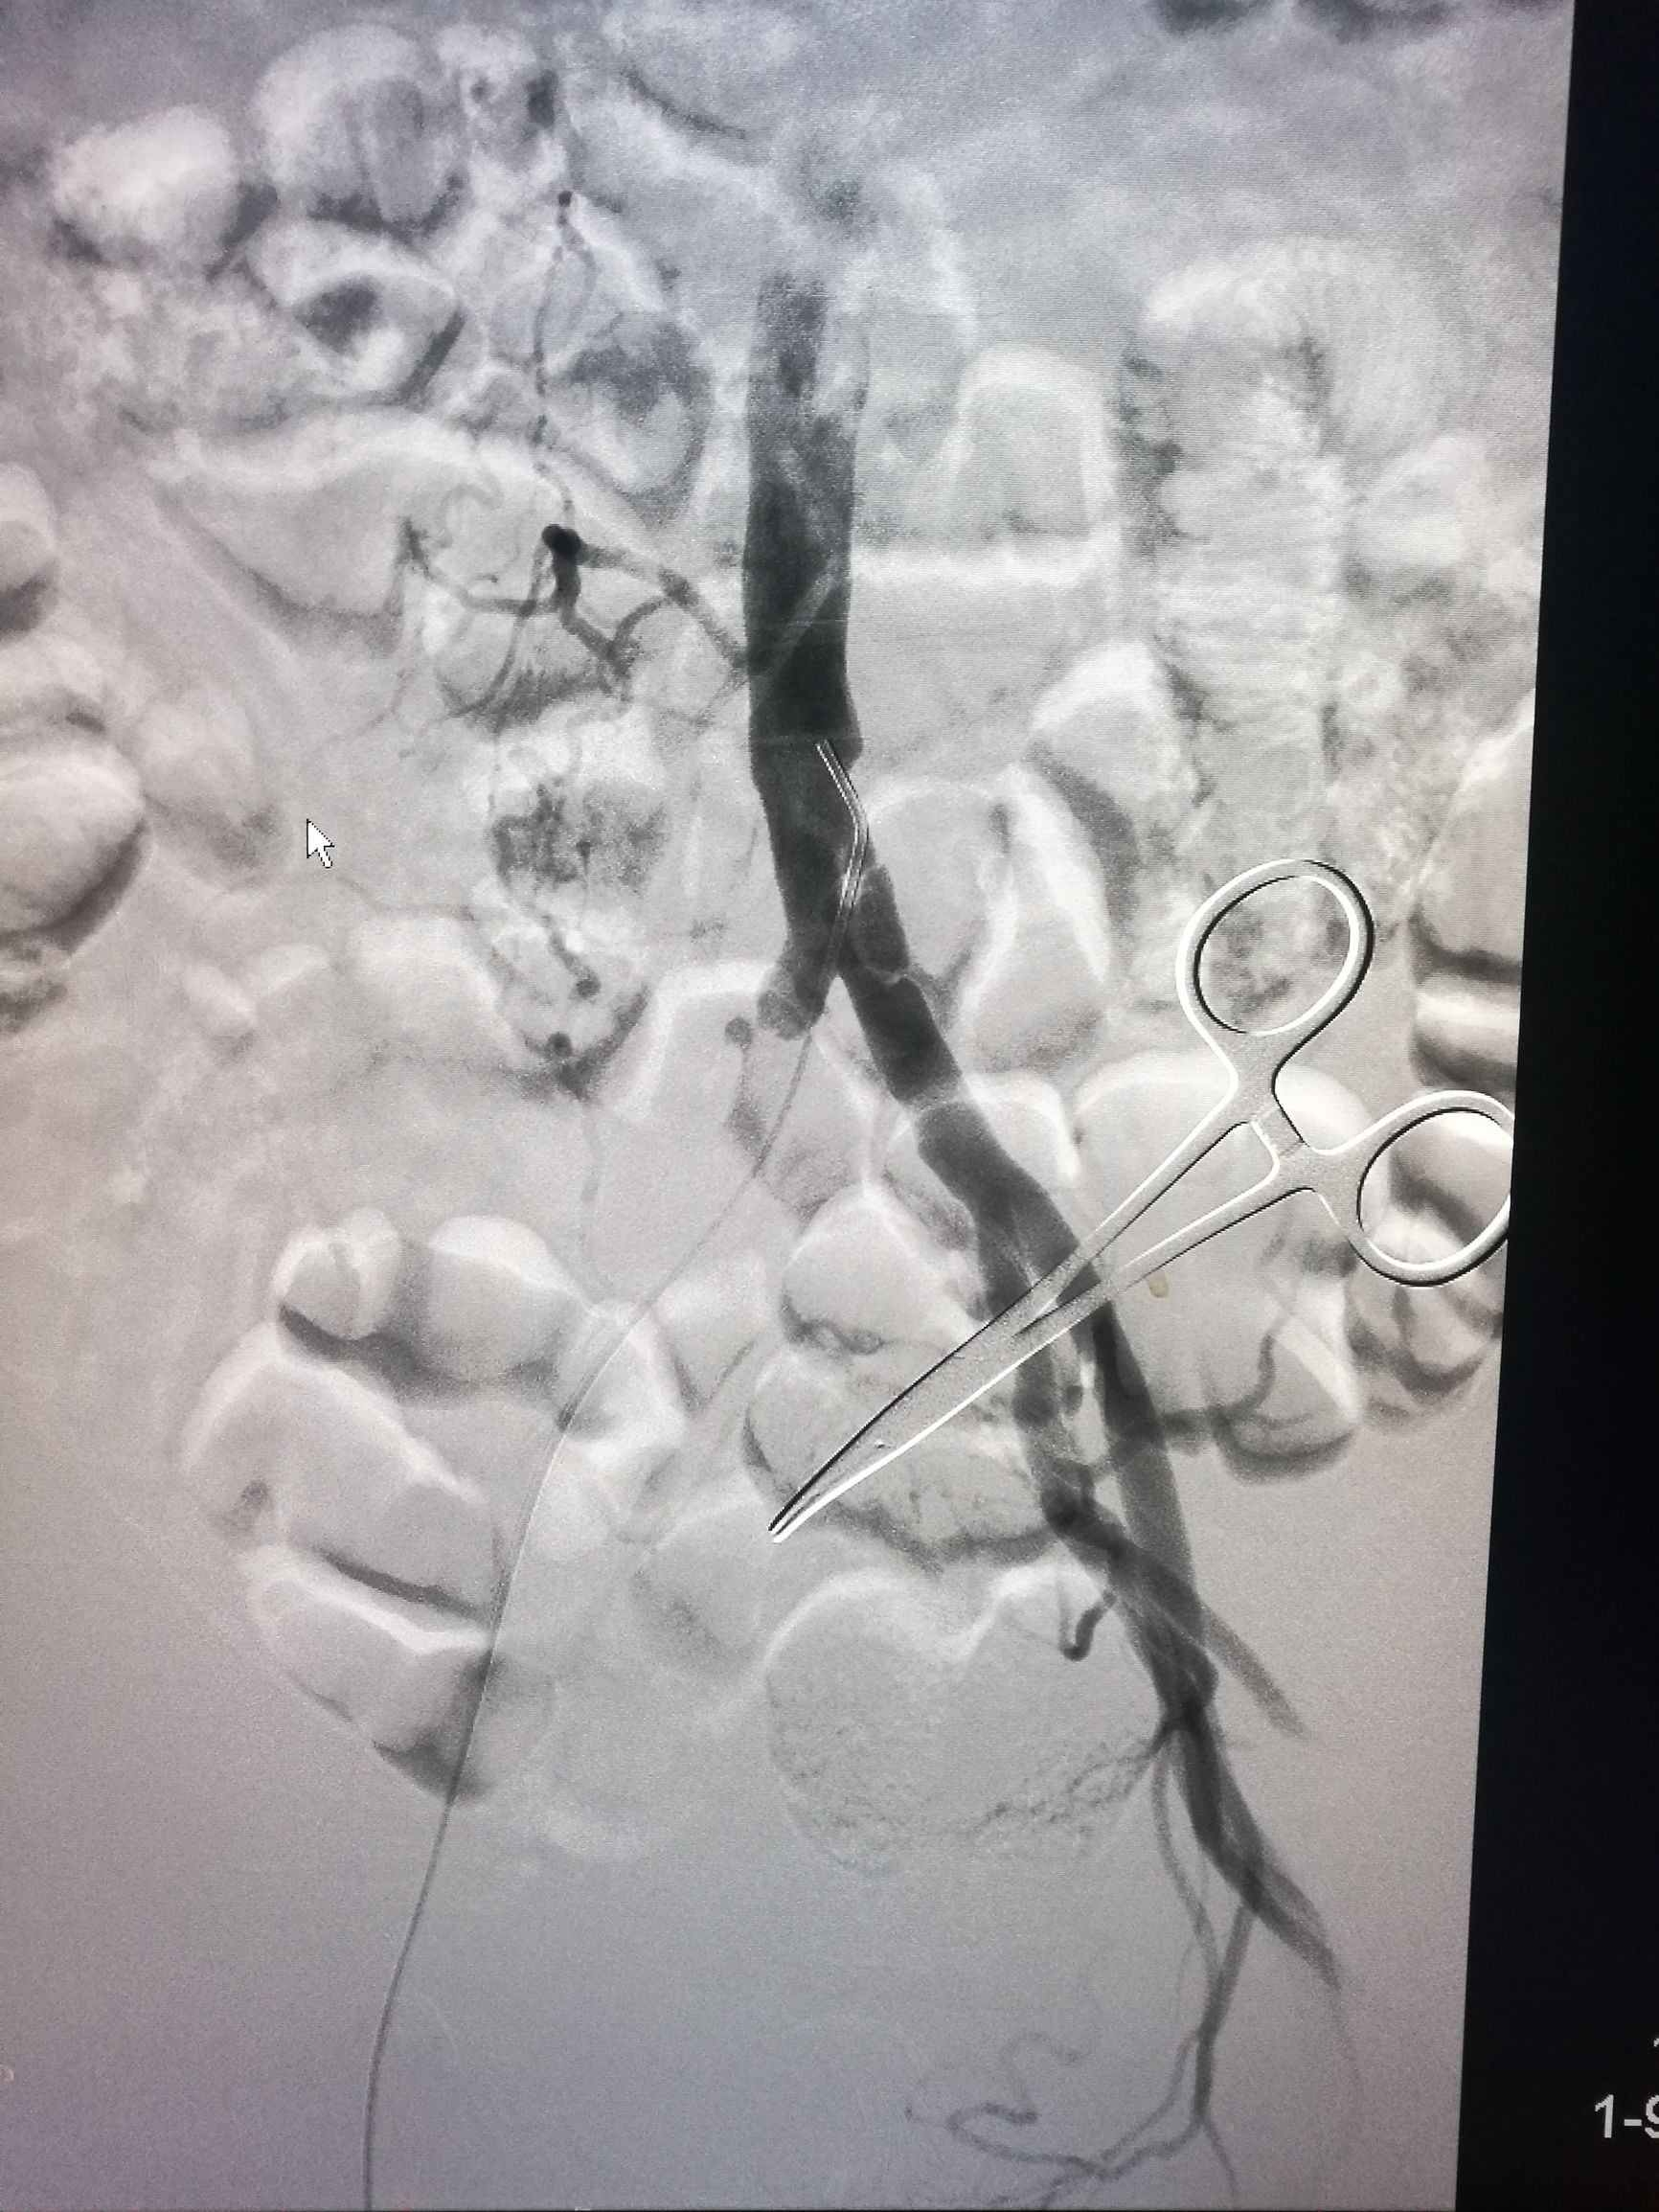

患者平卧位,常规消毒铺单,局麻下切开显露右侧股总动脉和股深动脉、股浅动脉。全身肝素化后,切开股动脉,对股浅动脉取栓后远侧回血好,对股深动脉反复取栓后出现汹涌回血。近端取栓后用导丝导管通过闭塞段到达腹主动脉下段,造影证实在真腔,用5*80mm球囊扩张后造影,髂动脉内有部分充盈缺损。植入巴德Fluency8*100和8*60覆膜支架后用7*60球囊扩张,造影管腔光滑(如图)。缝合动脉切口,关闭伤口,术毕。

术后右侧胫后动脉可以触及清晰搏动。